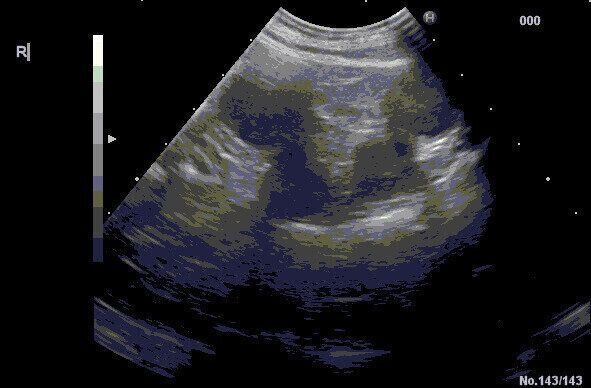

子宮蓄膿症のエコー写真

下痢やオシッコの症状から疑われる病気のひとつが「子宮蓄膿症」です。

これは、大腸菌などの細菌がさまざまな経路から侵入し、子宮の中で増殖して炎症を起こす、メス特有の病気です。若い犬でも見られますが、とくにシニア犬期で避妊手術を受けていない犬で多く見られ、発症すると子宮にたまった膿(うみ)が外陰部からもれることがあります。これを下痢と勘違いしてしまい、発見が遅れるケースが多いようです。